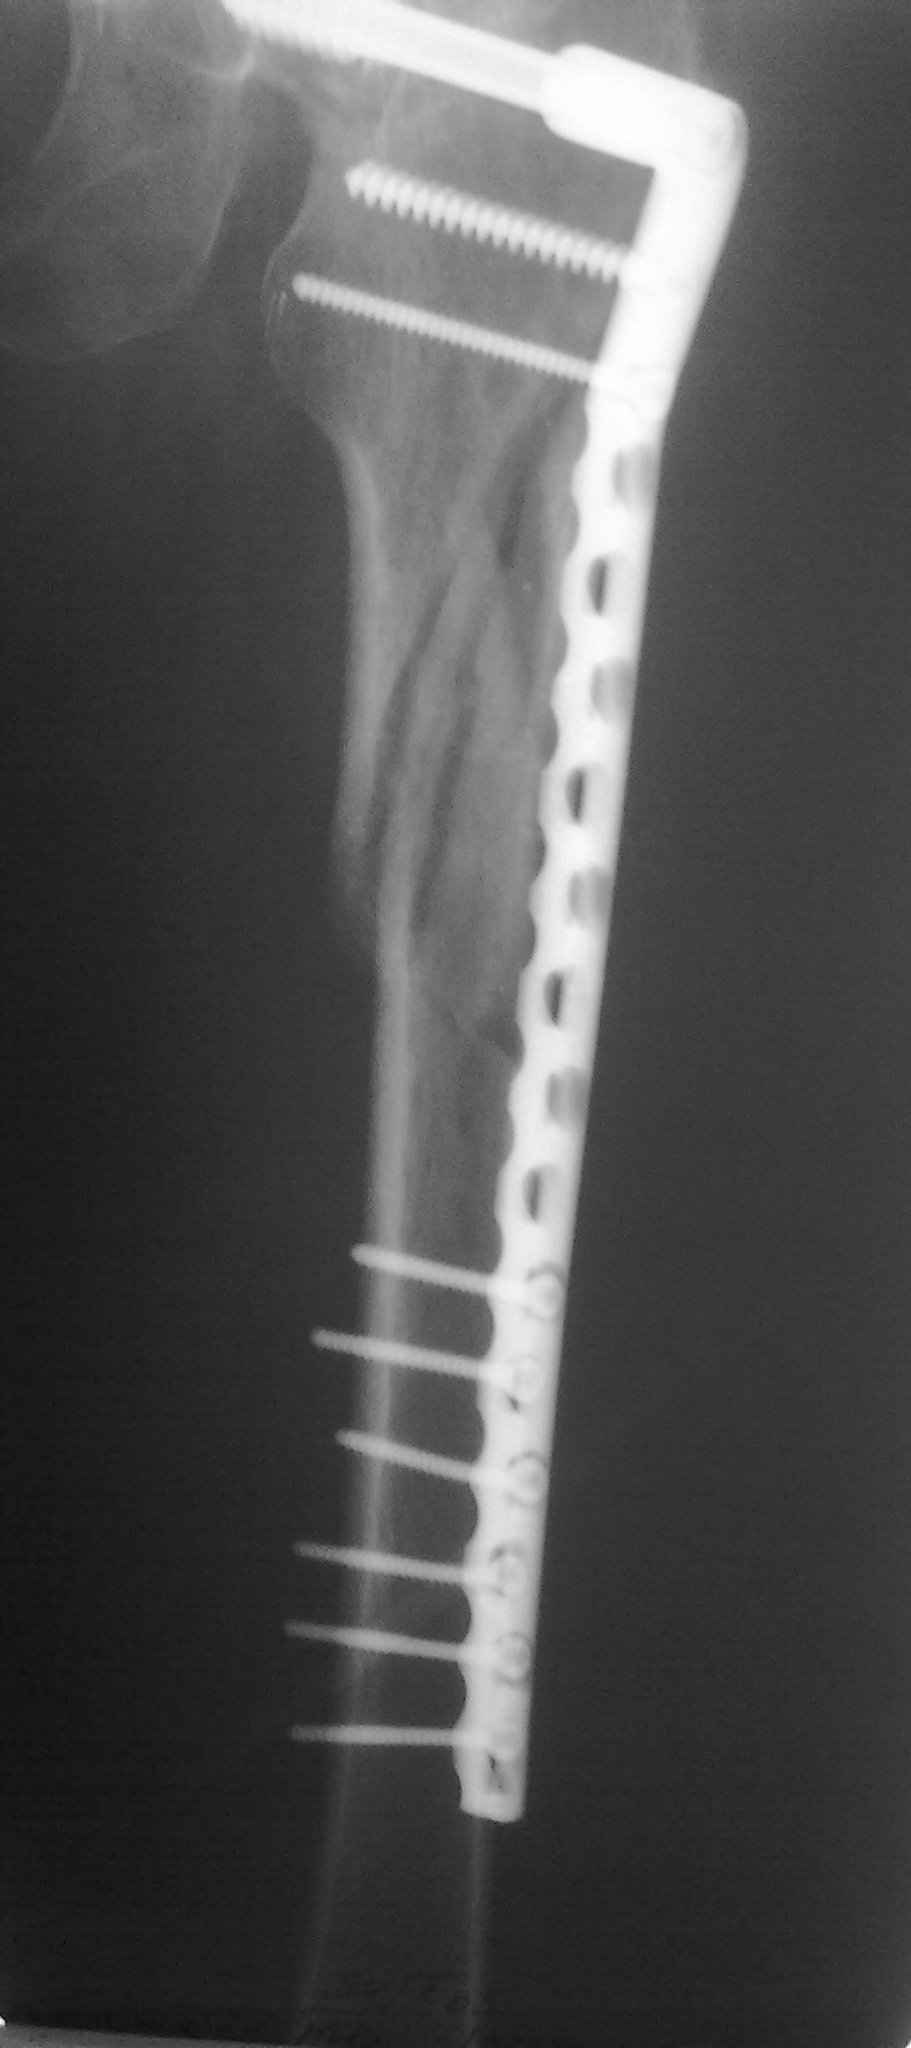

Пациент 83 года. Реконструктивный бедренный стержень Chm

Короткая версия 240 мм. Длинные начинаются с 260 мм? Попробуйте имеющуюся железку приложить к рентгенограмме - скорее всего, 260 мм будет маловато. Должна быть возможность связаться с поставщиком и поменять имеющийся гвоздь на аналогичный нужного размера.

А может для первого опыта подобрать и перелом и больную полегче, а в данном случае ограничиться DCS?

Мда...не самый удачный случай для начинаний... Думаю, 260 мм здесь явно не подойдет(коротковат), перед разрезом добивайтесь максимально возможной репозиции на столе, определитесь с точкой введения штифта(это принципиальный момент), если физически этой точки не существует, то все равно вводите штифт через то место, где она должна была бы быть, постарайтесь вводить штифт ориентируясь по наружному кортикалу и ни в коем случае не идите диагонально. Сам клинок вводите под контролем в аксиальной проекции (естессно, сначала смотрим спицу в прямой). Удачи!)))

День добрый! 240 мм однозначно короток, нужен миниум 300 мм, а то благие начинания заведут вас в ад осложнений. С диабетом на операции открывть ничего не нужно, только закрытая репозиция на ортопедическом столе под контролем ЭОПа. Без 100% анатомичной репозиции. Восстановить ось и ШДУ.

DHS, DCS , реконструкционный бедренный гвоздь всё это из другой оперы, не для этого перелома. Лучше потратьте время на поиски нужного удлиненного гамма-гвоздя и скорректируйте больную, чем не обдумано рисковать жизнью больной и своей репутацией (совестью).